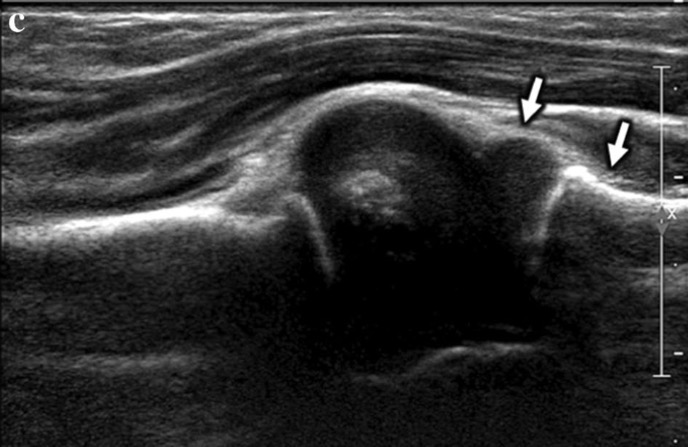

C. après le retrait du plâtre à 2 semaines:

- réduction du ligament annulaire (flèches blanches)

- restauration de l'apposition chondrale normale